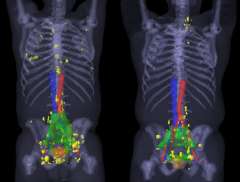

Larger image > Figure 1 : Example of a patient with metastatic castrate resistant prostate cancer responding to Lu177-PSMA radionuclide therapy.